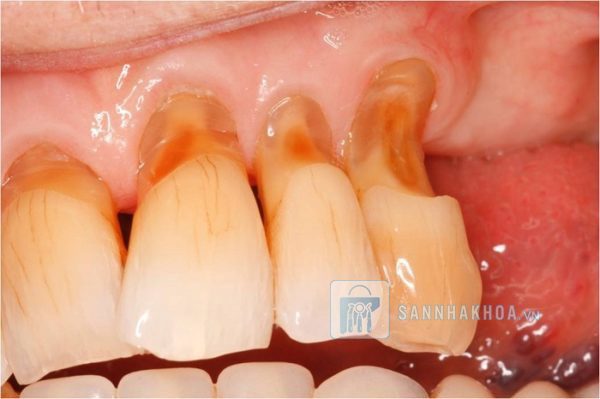

Mòn cổ răng là tình trạng vùng răng sát nướu bị mài mòn, hình thành các rãnh hoặc vết lõm rõ rệt. Đây là khu vực dễ tổn thương bởi tiếp xúc nhiều với lực cơ học từ việc vệ sinh răng miệng và các yếu tố khác. Ban đầu, tình trạng này có thể không rõ ràng, nhưng theo thời gian, mòn cổ răng gây ra nhiều vấn đề như ê buốt, nhạy cảm, và suy yếu cấu trúc răng.

Mòn cổ răng không chỉ ảnh hưởng đến sức khỏe mà còn làm mất đi vẻ đẹp tự nhiên của răng. Khi cổ răng bị lõm sâu, răng trở nên ngắn hơn, không đồng đều, và xuất hiện các rãnh xỉn màu. Lớp ngà răng bị lộ thường có màu vàng hoặc tối hơn men răng, khiến nụ cười trở nên kém rạng rỡ.